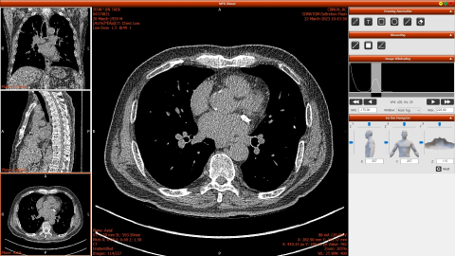

HEXA Pro는 인공지능(AI) 기반 흉부 CT 영상을 자동 분석해 폐, 심장, 간, 갑상선, 유방, 척추 등 주요 장기의 이상 질환을 동시에 탐지하는 차세대 의료영상 솔루션이다.

한 번의 CT 촬영만으로 6개 주요 장기를 분석하며, AI가 병변을 색상으로 표시해 이상 부위를 직관적으로 확인할 수 있다.

분석 결과는 전자문서 리포트(PDF)와 3D 이미지 형태로 제공되어 의료진이 환자의 상태를 한눈에 파악할 수 있으며, PACS 시스템과 연동되어 진료 현장에서 즉시 활용할 수 있다.

이번 전시에서는 병원 도입 사례와 HEXA Pro의 AI 분석 결과 리포트, 3D 시각화 이미지 등이 함께 전시되어, 방문객들이 HEXA Pro의 정확성과 효율성을 직접 확인할 수 있다.